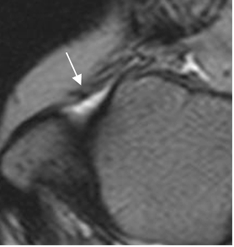

Fig 60. Esguince grado I.

RM axial en T2. Cambios inflamatorios rodeando el LPAA, el cual permanece intacto.